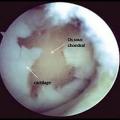

Lésion chondrale profonde

GONARTHROSE

CARTILLAGE ARTICULAIRE

GENOU